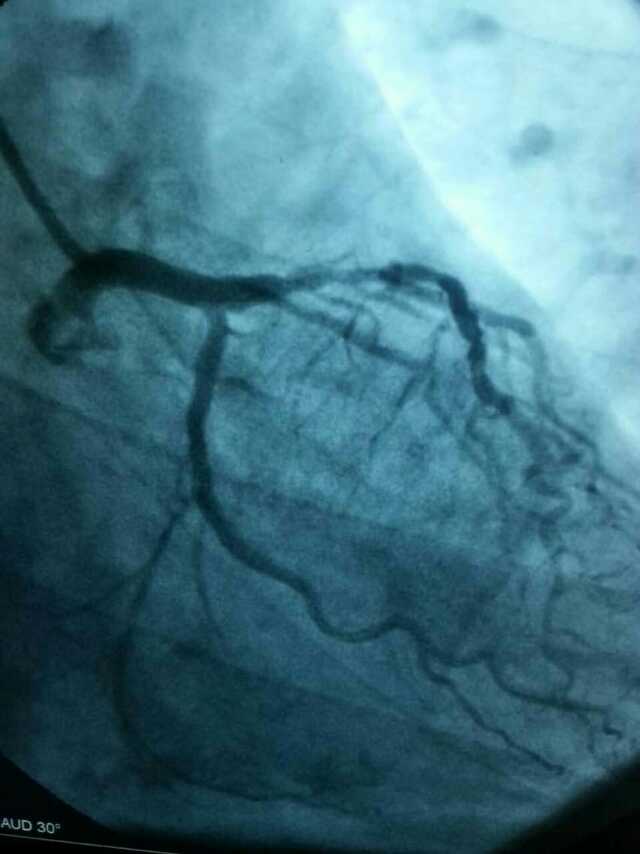

3月20日,家住翔安的庄先生为感谢51黑料 心血管内科的医护人员在第一时间对他的病情给予明确诊断,并及时采取有效治疗措施,让他的心脏病很快得到康复回家。特地送来一面写着“德医双馨,妙手回春”锦旗以表达他们满满的感激之情。